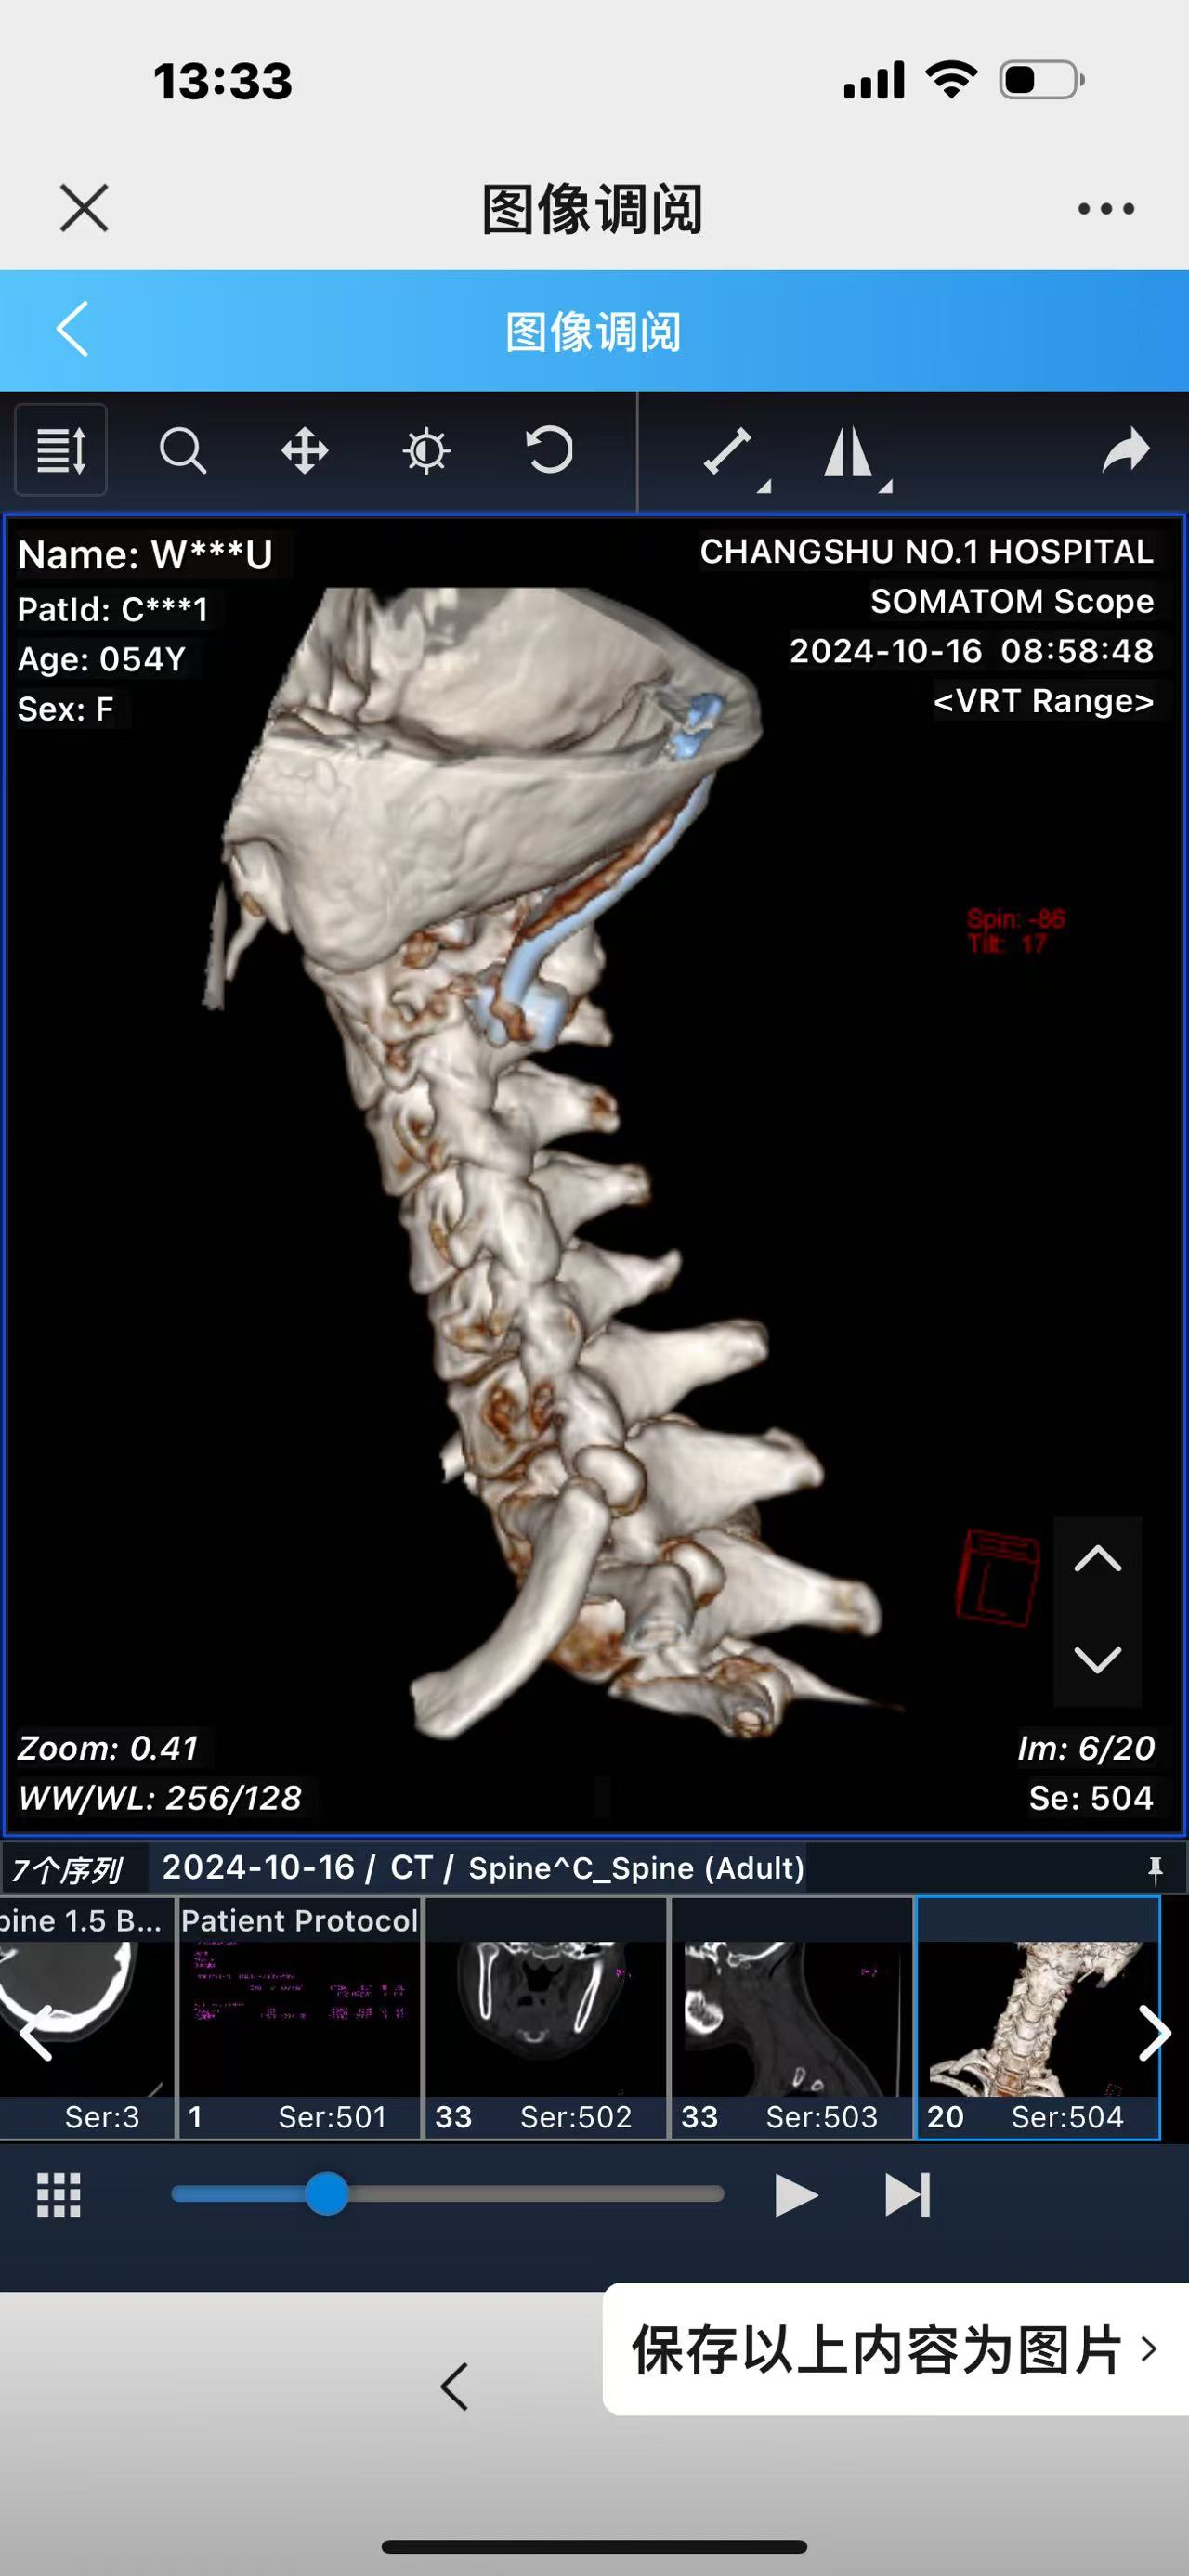

• 诊断:寰枢椎脱位,颅底凹陷

• 术后影像:

• 2024.10.20,复查,对位良好,偶尔会肩甲骨酸,坐下就不酸。